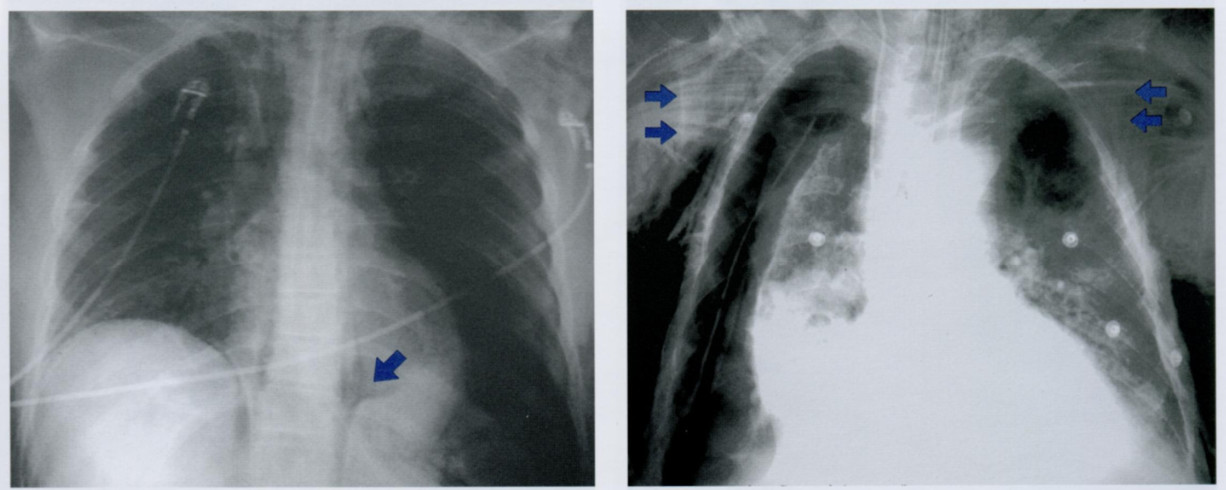

Данный снимок выполнен у одного и того же пожилого пациента с интервалом в 3 месяца. Обратите внимание на неравномерное утолщения ребер, отмеченные стрелками.

Дайте характеристику находке. Какие структуры грудной клетки наиболее часто поражаются?

Как отличить данную находку от костной мозоли после перелома?

Гематогенные метастазы - наиболее часто встречающиееся опухоли скелета грудной клетки у пожилых людей.

Особенно подозрительны кости, которые содержат костный мозг - ребра, грудина и позвоночник.

На повторном снимке мы видим прогрессию кортикального дефекта и увеличение размера метастаза.

На снимке слева ниже для сравнения показано веретенообразное утолщение после перелома ребра (костная мозоль), которое не сопровождается остеолическими изменениями кости. Важно визуально отличать костные мозоли и метастазы на ребрах.

На правом снимке также представлены участки остеолиза на телах грудных позвонков +/- снижение их высоты (отмечено стрелкой). При этом эти изменения не видны в ЗПП, поэтому показана БП.